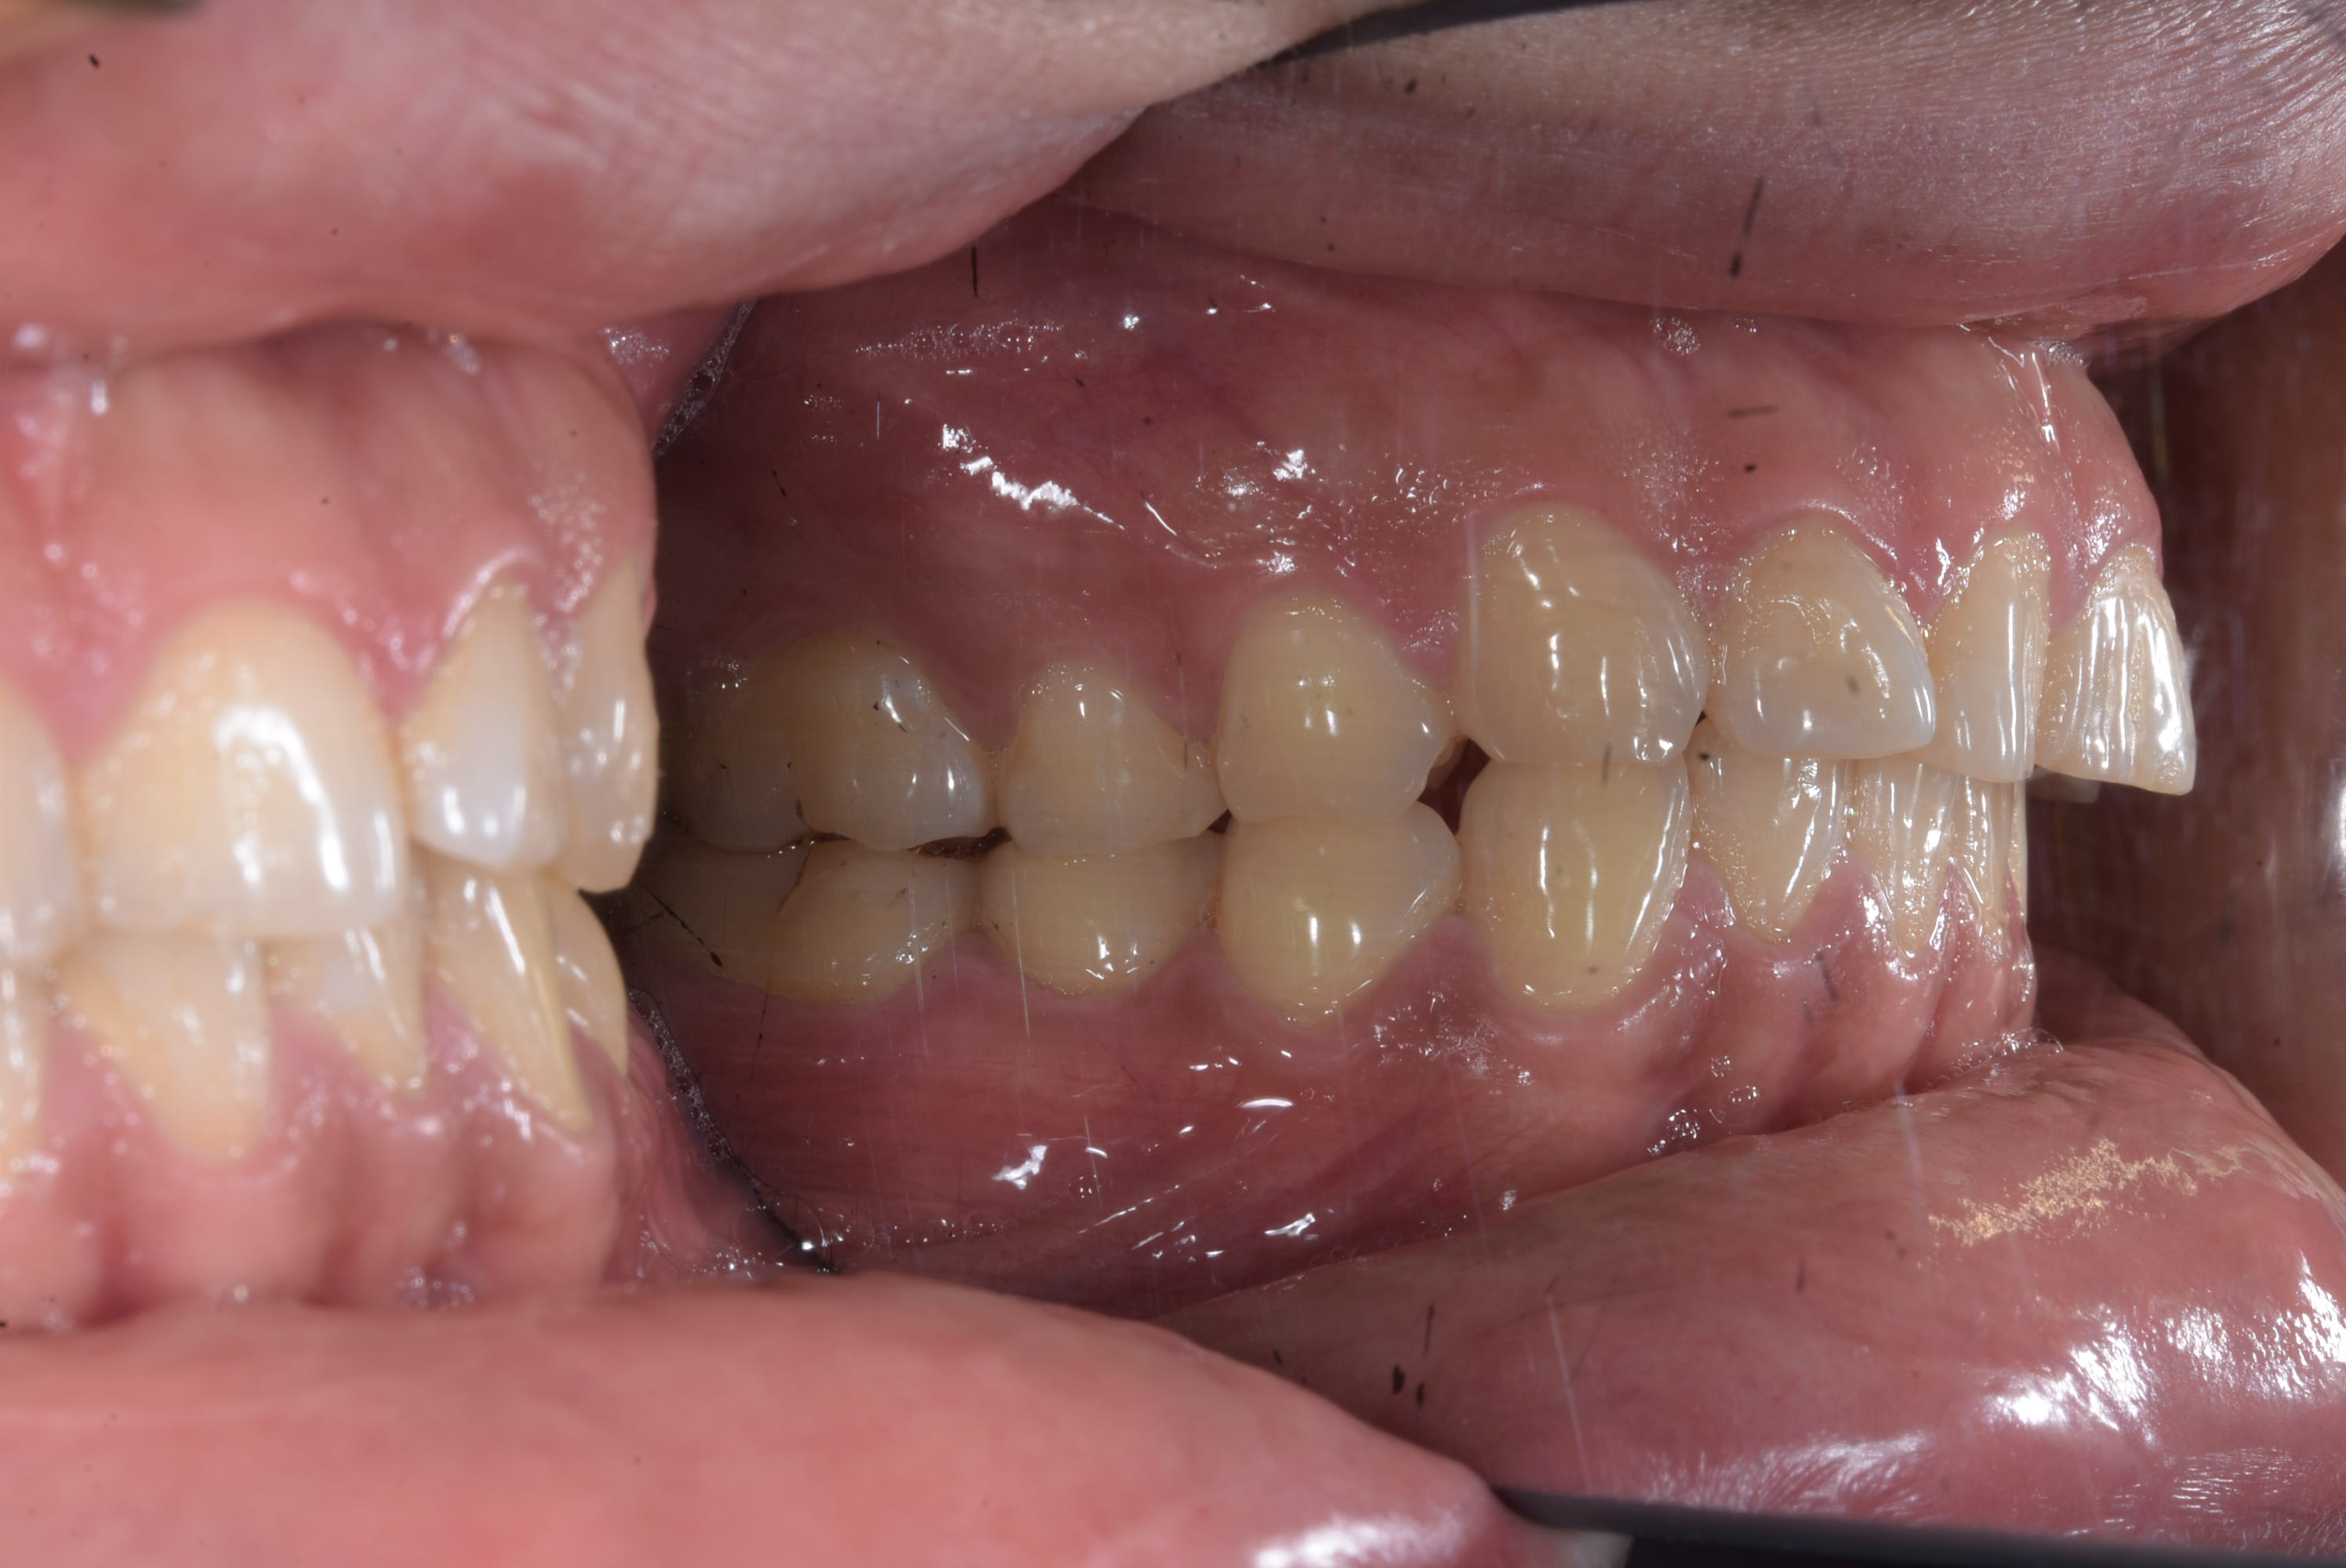

Ici le patient à besoin d'un traitement complet mais j'ai un soucie, la 46 est absente et la 47 versé et à une rotation.

J'ai un paquet de patient avec des 6 absente et des 7 versées , mettre un fil droit direct, surtout ici à cause de la rotation c'est t'exposer à un paquet de force parasite en gros :

- la molaire va vouloir s'egresser ( ici pas trop un soucie avec l'occlusion mais quand même à surveiller ) la j'ai put mettre direct un niti 18 et la semaine prochaine je devrais passer sur du niti 16 22 avec un set pour l'intrusion

J'ai mis le bracket en 45 en position apical et celui en 47 en position plus occlusal

- les prémo vont vouloir partir en lingual a cause de la rotation de la 7

- le bloc 3 a 5 va vouloir se verser en mésial

En aparté le patient aura plus que probablement un défaut paro sur la 47